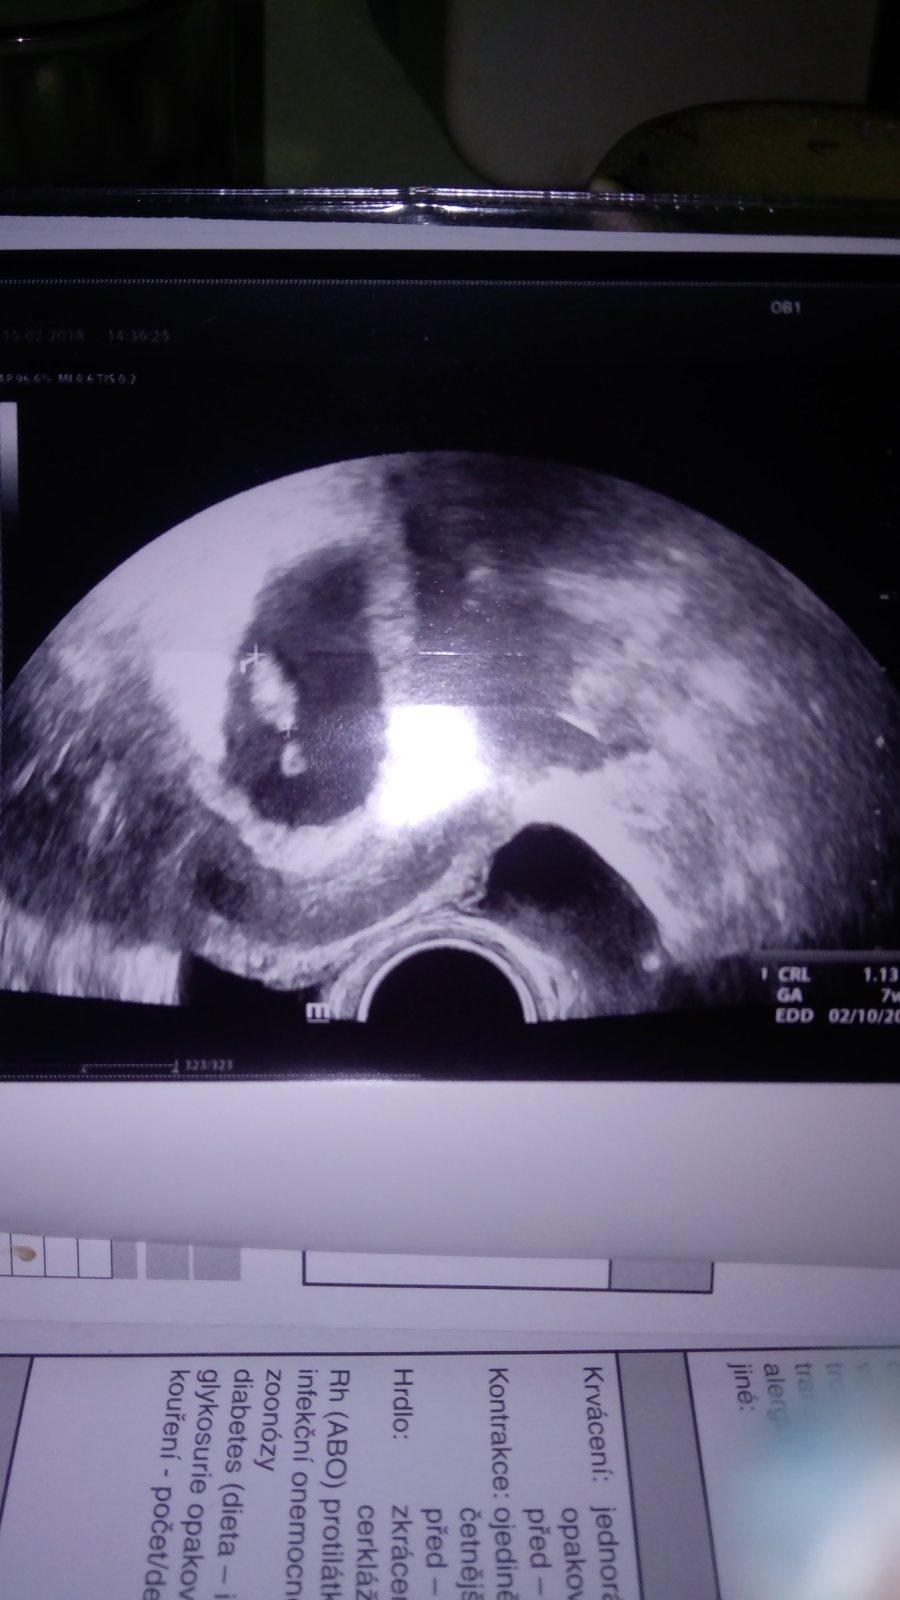

@fanunka 7+3